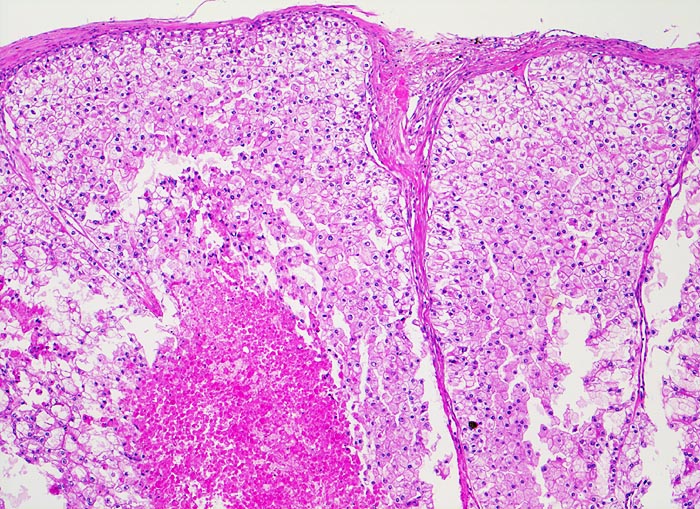

hellzelliges Nierenzellkarzinom

Das Karzinom bildet breite Trabekel aus planzenzellähnlichen Zellen mit reichlich klarem oder helleosinophilem Zytoplasma und deutlichen Zellgrenzen. Ausgedehnte Tumornekrose.

Der typische mikroskopische Aspekt hat dem hellzelligen (= klarzelligen) Nierenzellkarzinom seinen Namen verliehen. Das helle Zytopla kommt durch eine Akkumulation von Phospholipiden, Neutralfetten und Glykogen zustande.